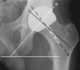

Medial dislocation of femoral component of total hip arthroplasty